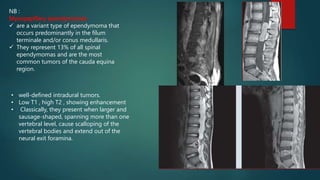

NB :

Myxopapillary ependymomas

 are a variant type of ependymoma that

occurs predominantly in the filum

terminale and/or conus medullaris.

 They represent 13% of all spinal

ependymomas and are the most

common tumors of the cauda equina

region.

• well-defined intradural tumors.

• Low T1 , high T2 , showing enhancement

• Classically, they present when larger and

sausage-shaped, spanning more than one

vertebral level, cause scalloping of the

vertebral bodies and extend out of the

neural exit foramina.